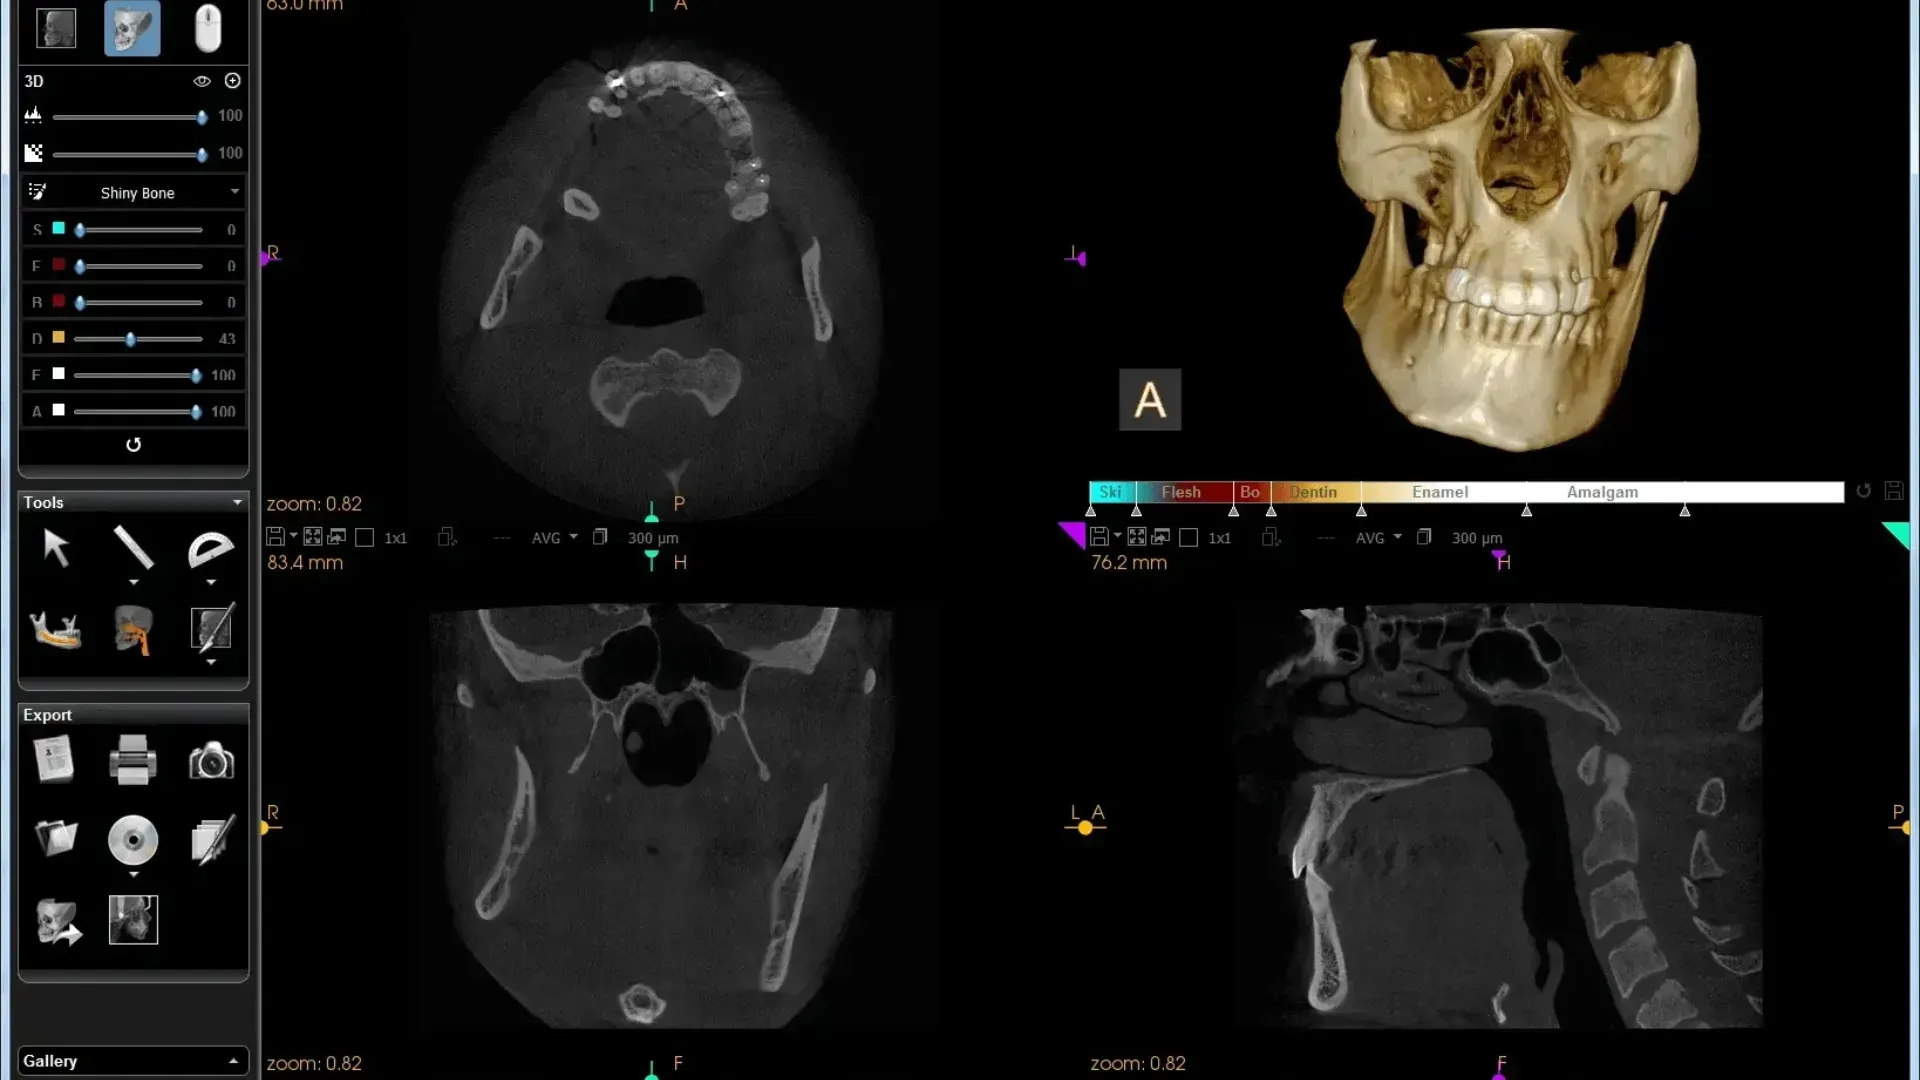

Radiografía Tridimensional 3D

Nos permite obtener imágenes detalladas de los huesos, dientes y estructuras anatómicas, facilitando un diagnóstico preciso y una planificación segura de tratamientos como implantes, ortodoncia o endodoncia.